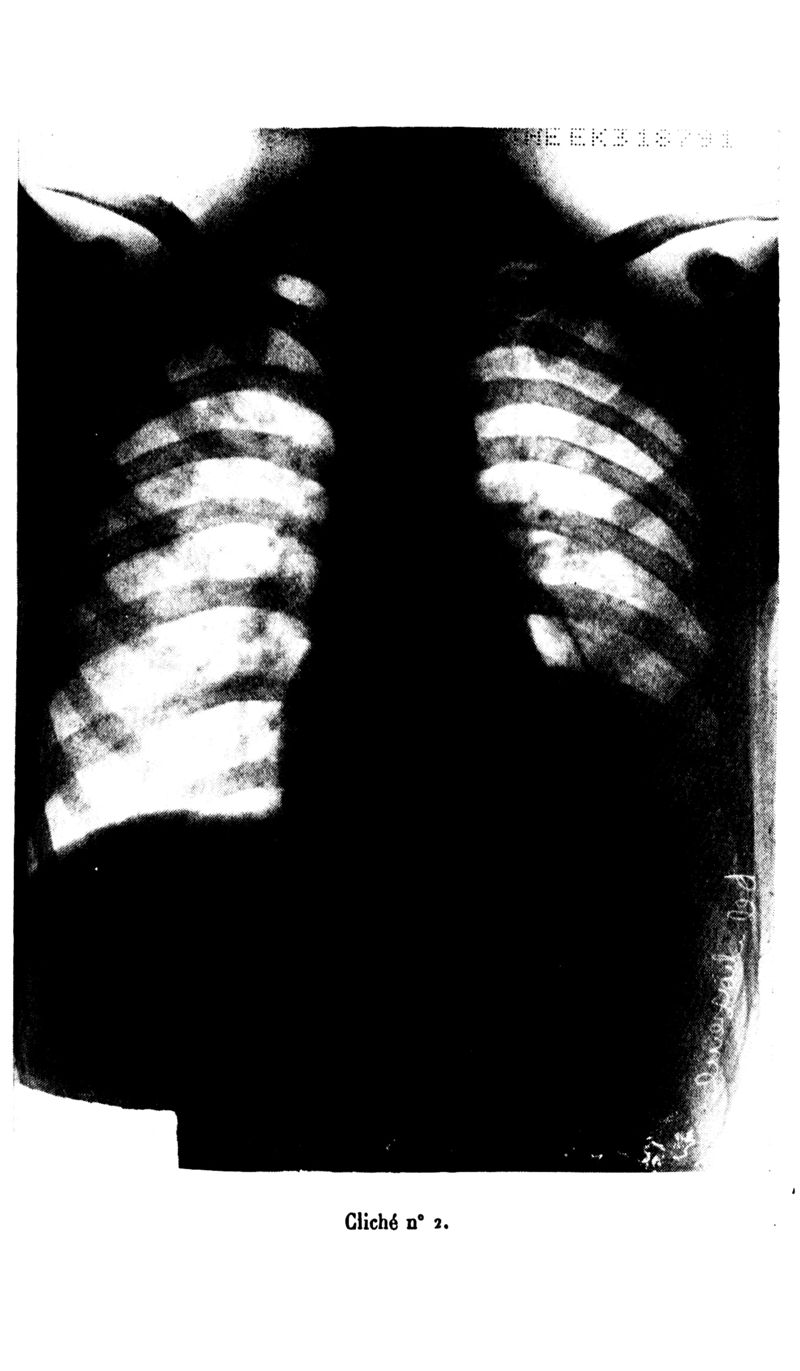

Archives de médecine et pharmacie navales

1938, n° 128. - Paris : Imprimerie nationale, 1938.